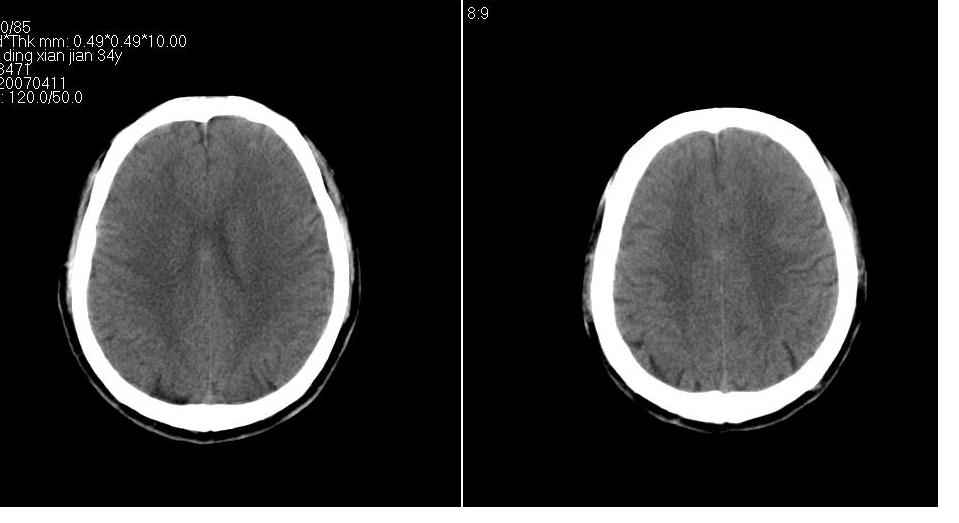

男 32岁,外伤。

大枕大池、左侧外侧裂池区蛛网膜囊肿

大枕大池、左侧外侧裂池区蛛网膜囊肿 。目前只能看到这些。

大枕大池,左外侧裂池蛛网膜囊肿

大枕大池、左侧颅中窝蛛网膜囊肿.